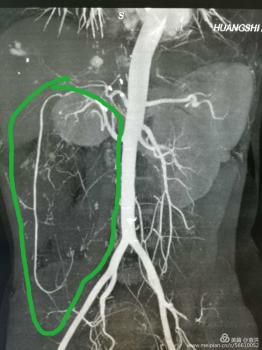

這一檢查讓婦科醫(yī)生也大吃一驚!醫(yī)生檢查時(shí)觸及腹部一硬質(zhì)包塊,無(wú)明顯邊界,上至劍突下,下至盆腔,兩側(cè)至腋中線,無(wú)壓痛,固定,說(shuō)明這包塊占據(jù)了患者整個(gè)腹腔,考慮來(lái)源于其它臟器,立即行全腹CT檢查??苫颊哂忻荛]空間綜合癥,一開(kāi)始拒絕CT檢查,醫(yī)生反復(fù)給患者做思想工作,并強(qiáng)調(diào)此項(xiàng)檢查的重要性,患者足足猶豫了兩天,才終于在醫(yī)護(hù)人員及家屬的鼓勵(lì)下順利完成了檢查。腹部CT提示,高度懷疑右腎有一顆脂肪肉瘤。

遂請(qǐng)泌尿外科會(huì)診協(xié)助診治,經(jīng)檢查,結(jié)合CT考慮腎周?chē)蚋鼓ず竽[瘤。最終診斷為:右腎巨大脂肪肉瘤。且腫瘤從腹腔延至盆腔,腹腔臟器受壓推移。醫(yī)生建議,子宮肌瘤多為良性,不影響生命,可暫緩手術(shù),但右腎巨大脂肪肉瘤必須盡快手術(shù)摘除。

經(jīng)血管重建提示:腫瘤供血豐富。泌尿外科建議:腫瘤來(lái)源于腎竇,手術(shù)風(fēng)險(xiǎn)極高。手術(shù)過(guò)程中,可能出現(xiàn)損傷動(dòng)脈出血,導(dǎo)致患者休克;取瘤后腹腔壓力下降,造成血壓下降,休克等風(fēng)險(xiǎn),術(shù)前須經(jīng)介入科行右腎血管栓塞治療。